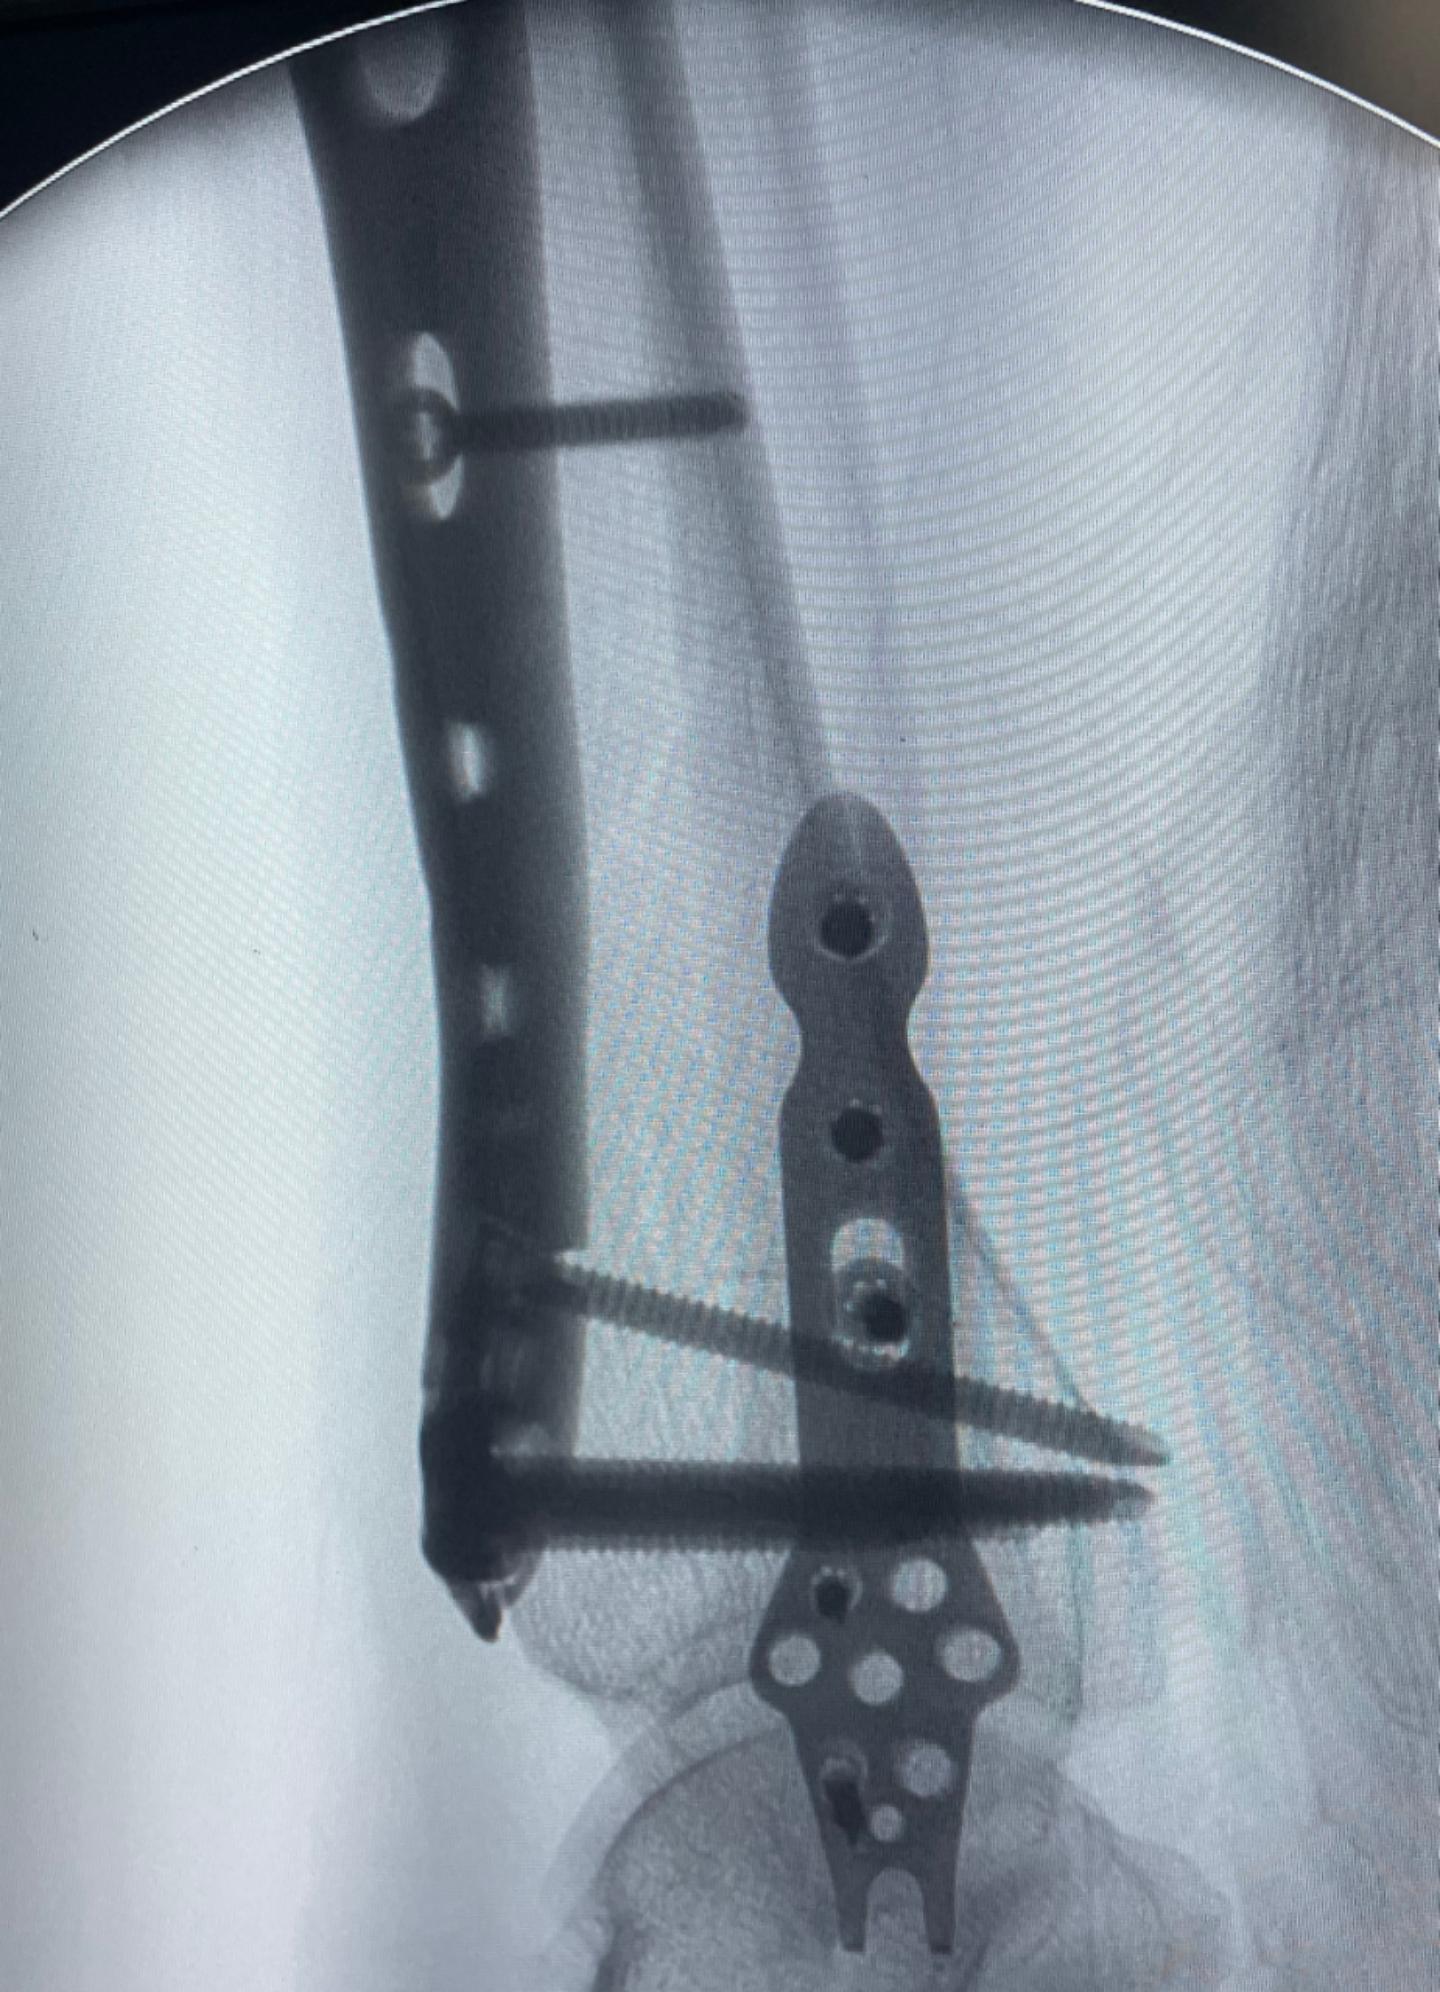

在确定王大娘左小腿软组织肿胀消退,局部擦伤可见好转的情况下,给王大娘进行可进行了左侧胫骨远端骨折闭合复位内固定手术,和左侧腓骨下段骨折闭合复位内固定手术,手术过程很顺利,两处骨折,两个切口,仅用时45分钟。术后继续给王女士冰敷,以防止局部软组织肿胀的进一步加重。

之后,术后复查时左小腿CT结果显示:左侧胫、腓骨骨折端复位良好,内固定位置良好。患者恢复得也很好,在术后第3天进行了左膝踝关节的主动屈伸功能活动,以预防后期的关节僵硬。